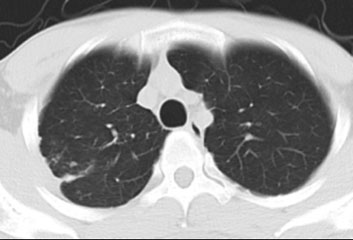

CT的全称是计算机断层扫描,即把人体水平分割成1.25mm~5mm的薄片,然后观察每一片上是否有病变。所以它是一个三维扫描,通过观察每一层的片子,肺部的病变不再有遮挡,一览无余。

胸片能发现的病变,CT一定可以发现,甚至看的更清楚。所以现在肺部检查首选CT。